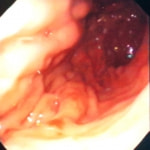

症例:炎症性ポリープ M.ダックス 10歳 オス

主訴:8ヶ月前から便が細くなり、血が混じることがある。その他、元気・食欲等、一般状態は良好。

経過:超音波検査にて直腸壁の肥厚(5㎜)が認められた。また、直腸検査で直腸全周に結節状病変を触知し、出血も確認された。消炎剤、抗生剤、整腸剤による治療への反応が長期的に悪いため、生検も含めた内視鏡検査を実施した。

内視鏡検査:肛門付近の直腸全周に、炎症および出血を伴う結節状病変を多数認めた。

病理検査:直腸の病変は、良性の非腫瘍性病変の一つである“炎症性ポリープ”と診断された。

診断後経過:炎症性ポリープは多発する傾向や腫瘍に転化する可能性があるため、消炎剤、抗生剤、整腸剤による内科療法を継続しながら、現在プルスルー法による外科的摘出術を検討中。